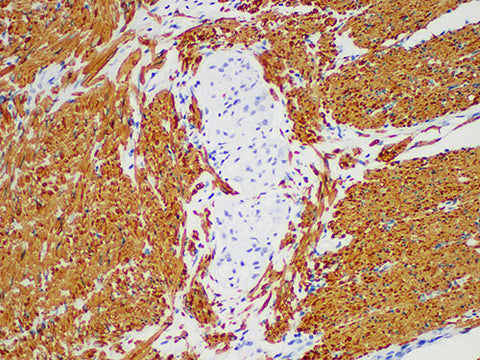

Actin pan Monoclonal Antibody Stored at -20°C

Applications IHC-P

Tissue Specificity Colon cancer

Actin pan is a kind of microfilament proteins with contractile ability, which are widely expressed in almost all myotype cells. Actin is a broad-spectrum actin, which is mainly used to detect skeletal muscle, smooth muscle, vascular smooth muscle, myocardial and myogenic tumors, including leiomyoma, leiomyosarcoma and rhabdomyosarcoma, myoepithelial cells and myoepithelioma.